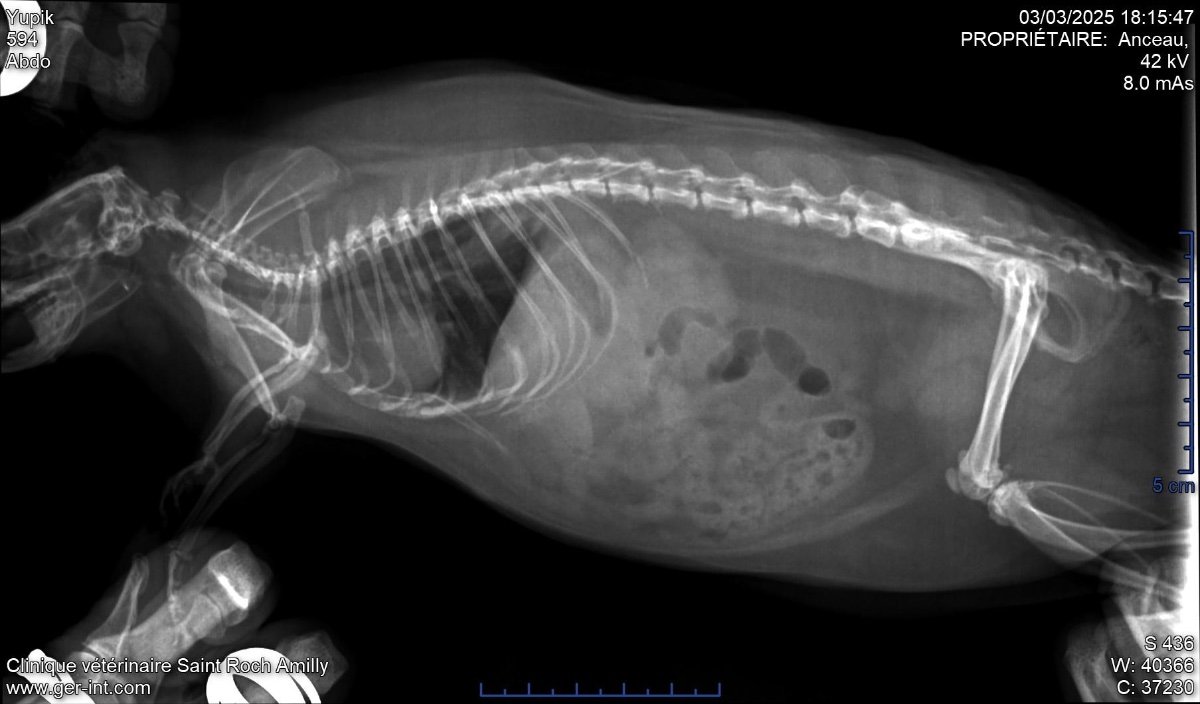

Résultats de la radio :

Présence d’une masse au niveau de l’estomac, vers la sortie de l’estomac. C’est en appuyant à cet endroit qu’il ronfle et fait des pouics, parfois même un éternuement.

Une autre masse a été détectée près du cœur, au-dessus des poumons.

Autre chose : il ronfle lorsque son cœur s’accélère, que ce soit après un repas, une émotion forte ou une sortie. Il reste très gourmand, ce qui est rassurant. Mais je me demande si ses symptômes sont liés à deux tumeurs ou masses : l’une appuyant sur le cœur, l’autre sur l’estomac. Il tousse parfois mais ne semble pas malade.